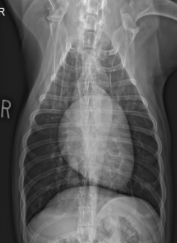

ID View

DV